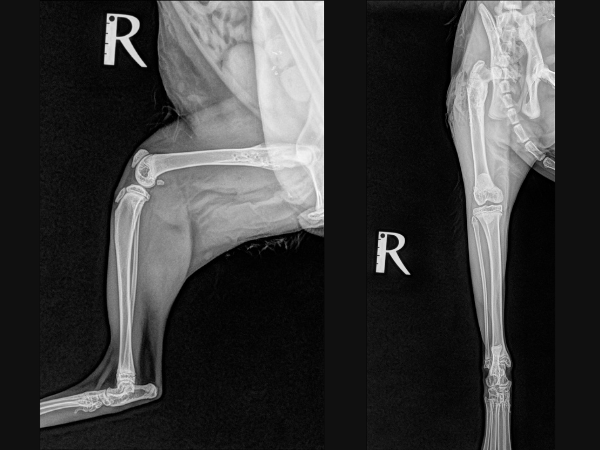

<手術前のレントゲン>

右大腿骨近位斜骨折しています。

▼手術前